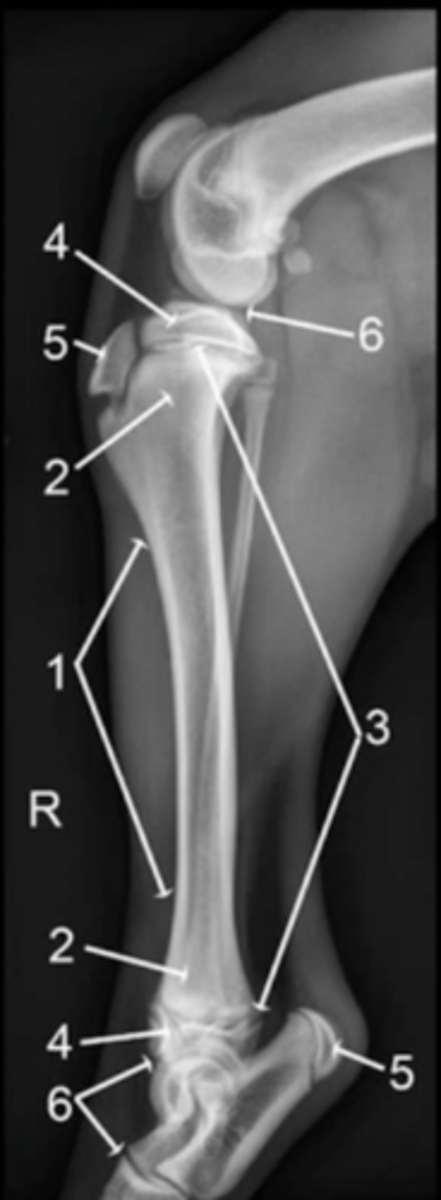

diaphysis

1

metaphysis

2

physis

3

epiphysis

4

apophysis

5

joint

6